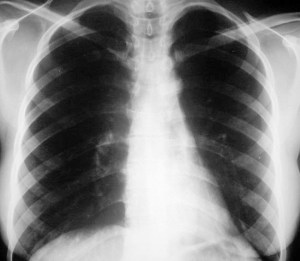

SIGNO DEL DOBLE CONTORNO

Signo de crecimiento de la aurícula izquierda en la radiografía posteroanterior de tórax. La aurícula izquierda no forma parte normalmente del contorno cardiaco derecho en esta proyección; sin embargo, cuando aumenta de tamaño, produce un segundo contorno (flecha negra), además del de la aurícula derecha (flecha blanca).

La radiografía muestra este signo en un enfermo mitral, así como el aumento de tamaño de la silueta cardiaca.